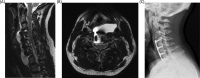

Objectives: Rare complications of cervical spine surgery are inherently difficult to investigate. Pseudomeningocoele (PMC), an abnormal collection of cerebrospinal fluid that communicates with the subarachnoid space, is one such complication. In order to evaluate and better understand the incidence, presentation, treatment, and outcome of PMC following cervical spine surgery, we conducted a multicenter study to pool our collective experience.

Results: Thirteen patients (0.08%) developed a postoperative PMC, 6 (46.2%) of whom were female. They had an average age of 48.2 years and stayed in hospital a mean of 11.2 days. Three patients were current smokers, 3 previous smokers, 5 had never smoked, and 2 had unknown smoking status. The majority, 10 (76.9%), were associated with posterior surgery, whereas 3 (23.1%) occurred after an anterior procedure. Myelopathy was the most common indication for operations that were complicated by PMC (46%). Seven patients (53%) required a surgical procedure to address the PMC, whereas the remaining 6 were treated conservatively. All PMCs ultimately resolved or were successfully treated with no residual effects.

Conclusions: PMC is a rare complication of cervical surgery with an incidence of less than 0.1%. They prolong hospital stay. PMCs occurred more frequently in association with posterior approaches. Approximately half of PMCs required surgery and all ultimately resolved without residual neurologic or other long-term effects.